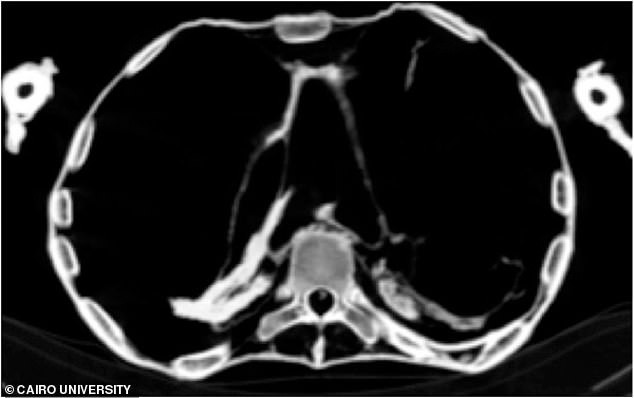

Người phụ nữ này bị xơ vữa động mạch vành trái và phải, động mạch cổ, động mạch chủ bụng, động mạch chậu gốc và chi dưới.

Căn bệnh nguy hiểm này đã làm hẹp lòng mạch và tắc nghẽn mạch máu dẫn đến cái chết đầy đau đớn của "người phụ nữ la hét". Vài giờ sau khi "người phụ nữ la hét" tử vong, người ta mới phát hiện sự việc.